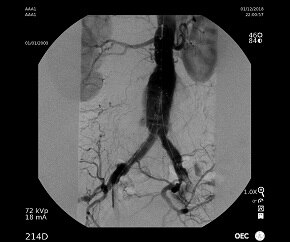

Ангиограмма

Ангиограмма аорты